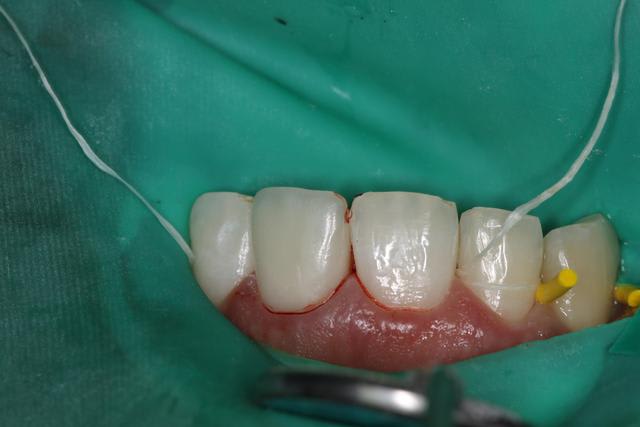

06/01/2012 à 01h31

J'ai posé un autre cas d'Emax avant hier pas trop mal, patient content.

Sur 21 très large sur laquelle j'ai fait apexification au MTA.

(Sur la photo, ce n'est pas un herpes, mais une chute en luge au ski...)

Variolink II teinte A3